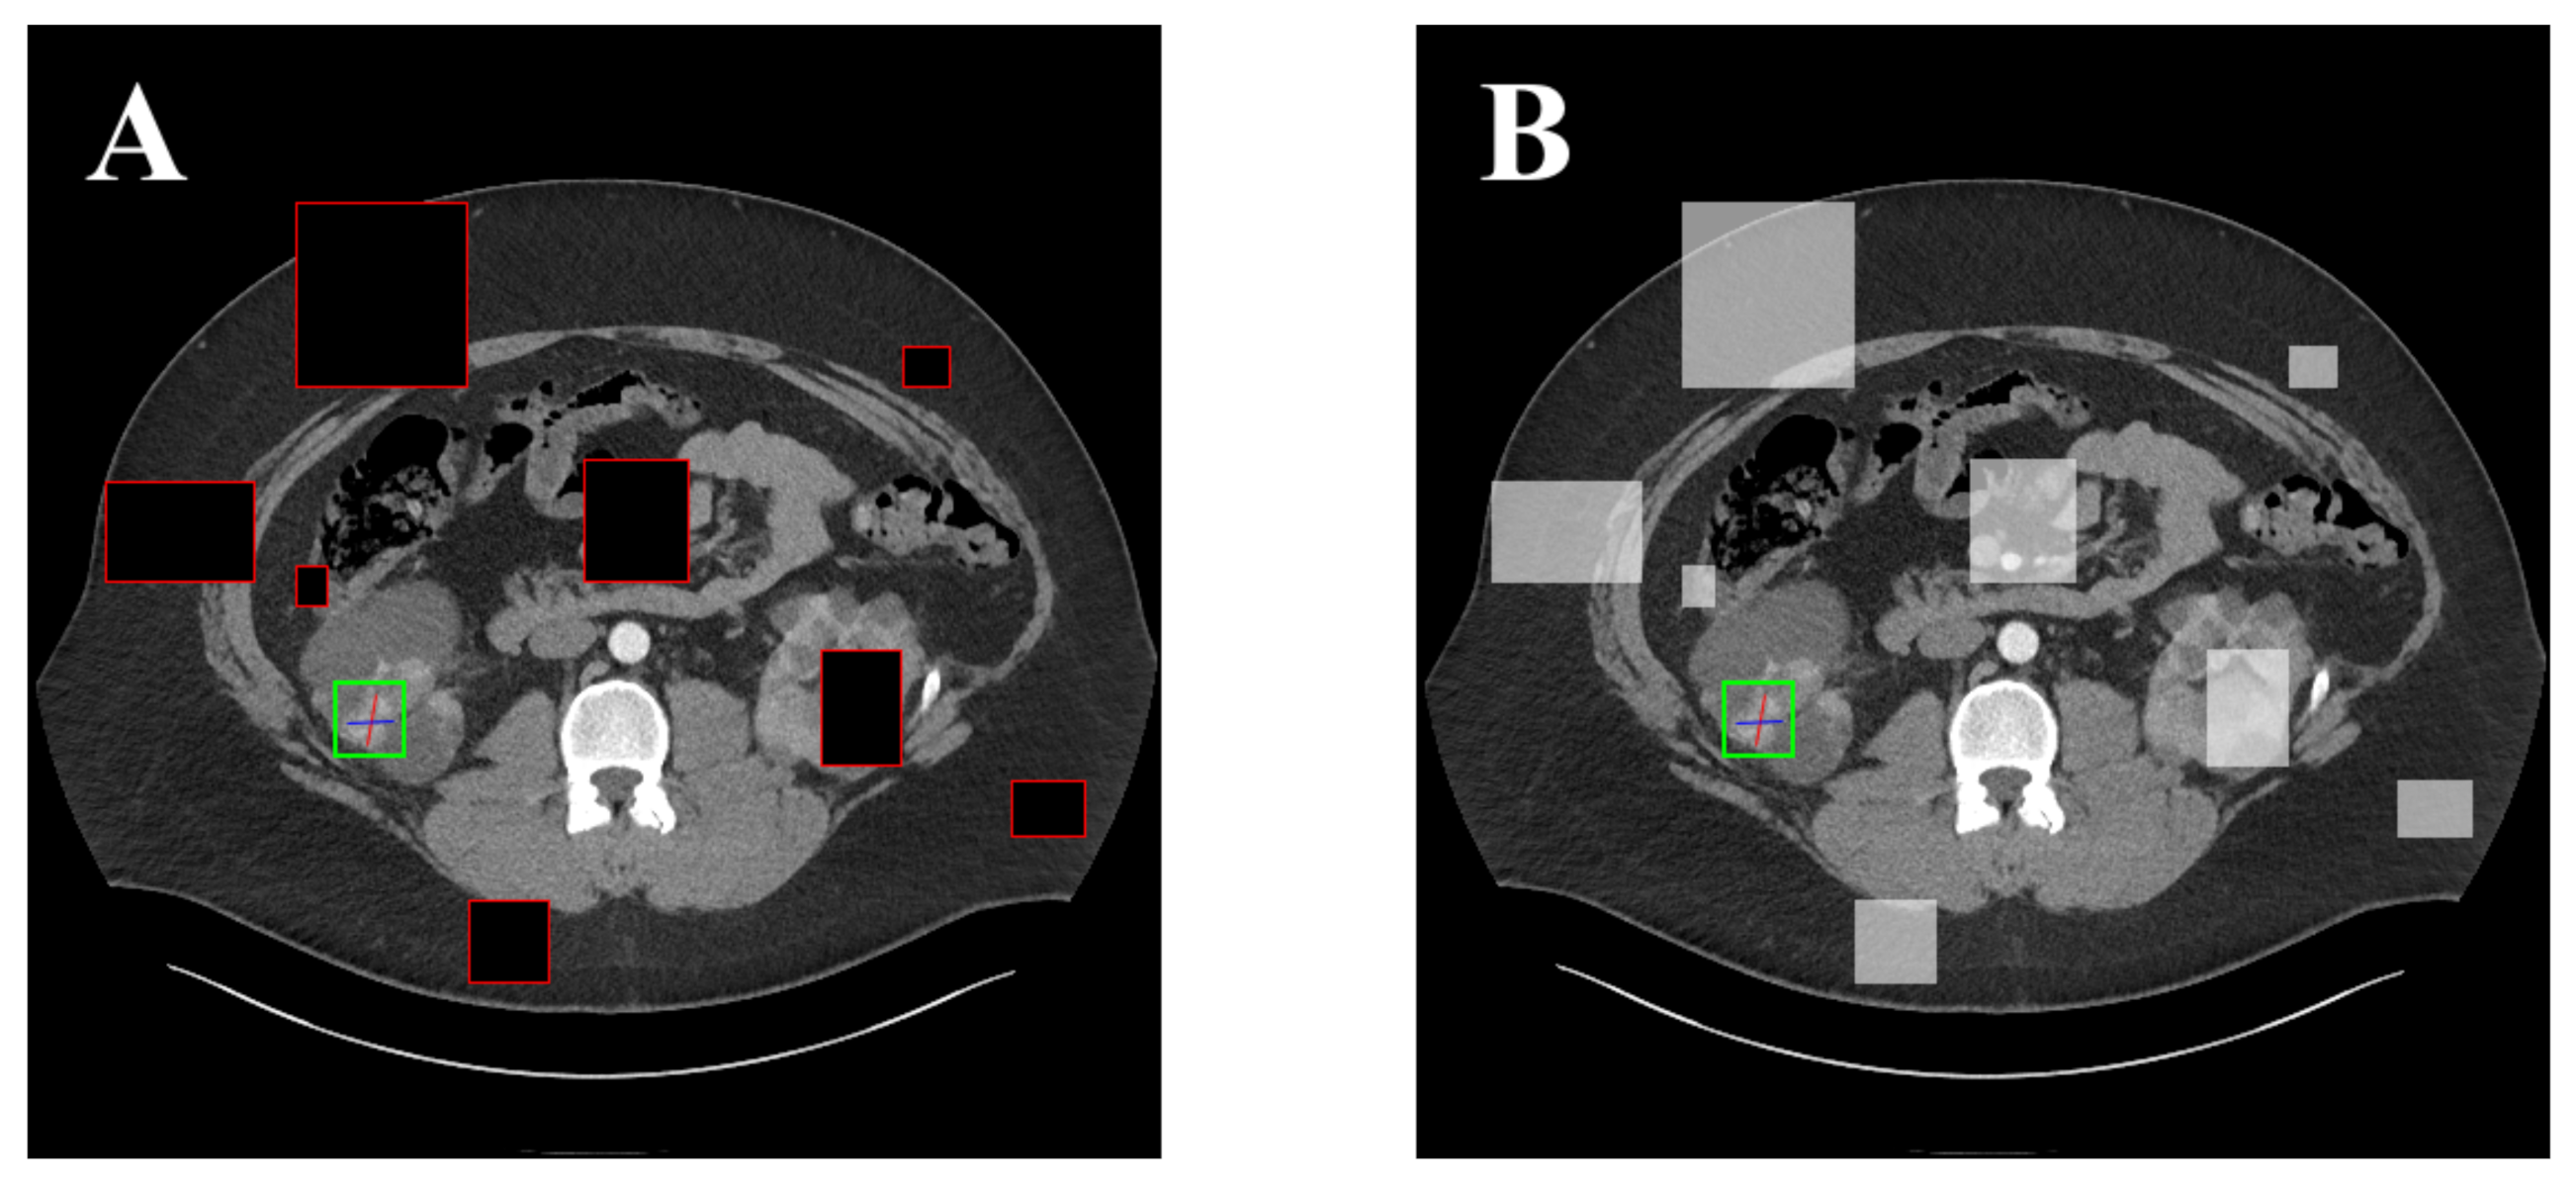

5.2. Detection Results

For further comparison, we extracted six images from the CT image series of DeepLesion. These images were taken from different sites of lesions and different areas of lesions, showing the detection results of the comparison model as comprehensively as possible. Figure 10, Figure 11, Figure 12, Figure 13, Figure 14, Figure 15, Figure 16, Figure 17, Figure 18 and Figure 19 show the detection results. All green boxes represent ground truth; red boxes denote predicted bounding boxes. It can be seen that Faster-RCNN performs very poorly on small lesions and lesions that are not easy to identify, while YOLO v3, YOLO v4, and SSD series perform relatively well. However, the aspect regression of the bounding box at small lesion locations is still not accurate. On the other hand, EfficientDet, Mask-RCNN, and YOLO v5 perform relatively well and detect lesions accurately. This may be related to the attention extraction module in these networks.

Figure 18.

The detection results of SGDN 300 in the DeepLesion dataset. The green box marks the location of the lesion.

Figure 19.

The detection results of SGDN 512 in the DeepLesion dataset. The green box marks the location of the lesion.

Our model, especially SGDN 512, outperforms the previous models by detecting lesions with high accuracy for non-minimal lesions. Although there is still room for improvement, it has outperformed other models. On the one hand, we augment the image with the GAN model before it is fed into the backbone. On the other hand, we add the GAN model to the attention extraction module of the model, which can significantly improve the model’s robustness.

According to Figure 10, Figure 11, Figure 12, Figure 13, Figure 14, Figure 15, Figure 16, Figure 17, Figure 18 and Figure 19, the proposed model produces the most comprehensive detection results compared to other models. However, there are still a few cases where the shortcomings of SGDN can be seen: the arrows in Figure 19 show that our model is still not accurate at the edge of the lesion. In addition, from these figures, we can see that all the comparison models perform very poorly at the site of arrow A. The difference between the predicted box and the ground truth given by our model at arrow A is the largest compared to other recognition results.